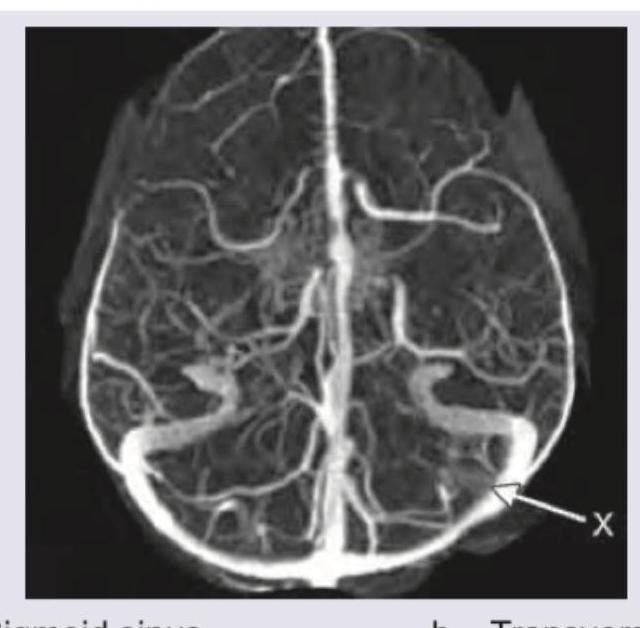

The structure marked as $X$ in the below shown MR venography of the brain is:

Explanation: ***Sigmoid sinus*** - The image shows a **venogram**, highlighting the venous structures of the brain. The structure marked 'X' exhibits the characteristic **S-shaped curve** that defines the sigmoid sinus. - The sigmoid sinus is a continuation of the **transverse sinus** and drains into the **internal jugular vein**. *Transverse sinus* - The transverse sinuses are typically observed as straight, elongated structures running horizontally along the posterior aspect of the brain, a path distinct from the curved structure marked 'X'. - They receive blood from the superior sagittal sinus and often from the inferior sagittal sinus via the straight sinus, converging at the **confluence of sinuses (torcular herophili)**. *Basal vein of Rosenthal* - The basal vein of Rosenthal is a deep cerebral vein, typically running anterior to the brainstem and draining into the **great cerebral vein of Galen**. - Its location and appearance are different from structure 'X', which is a large superficial dural venous sinus. *Torcular herophili* - The torcular herophili, also known as the **confluence of sinuses**, is the junction point of the superior sagittal, straight, and transverse sinuses. - It would appear as a central convergence point at the back of the skull, not a distinct, curved sinus like 'X'.